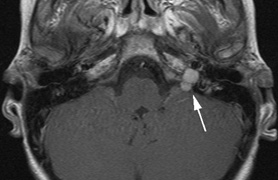

1. Schwannomas most commonly affect the fifth cranial nerve (CN), but any cranial nerve may be affected. In contrast to vestibular schwannomas (CN VIII), these typically do not grow large.84,90 Vestibular schwannomas (acoustic neuromas) are the classic finding in NF2 (Fig. 7). The risk for malignant transformation is low, but may be higher with radiation exposure.84,94

Fig. 7. Neurofibromatosis type 2: Images of a 12-year-old boy with deafness and weakness in his arms and legs, whose father has bilateral deafness. Axial T2-weighted (a) and postcontrast axial (b) T2-weighted images reveal bilateral vestibular schwannomas, which are also known as acoustic neuromas (arrows). This is the classic finding of NF2. (b, c) Bilateral schwannomas are seen in Meckel's cave (arrowheads) and a (d) lower left cranial nerve schwannoma extends into the pars nervosa of the jugular foramen (arrow). (e) A part cystic and part solid enhancing ependymoma in seen within the cervical cord and medulla and within the distal cord and conus. (e, f) Thoracic schwannomas are present at numerous levels (arrowheads). Marked enhancement and thickening of the roots within the cauda equina also represent multiple schwannomas.